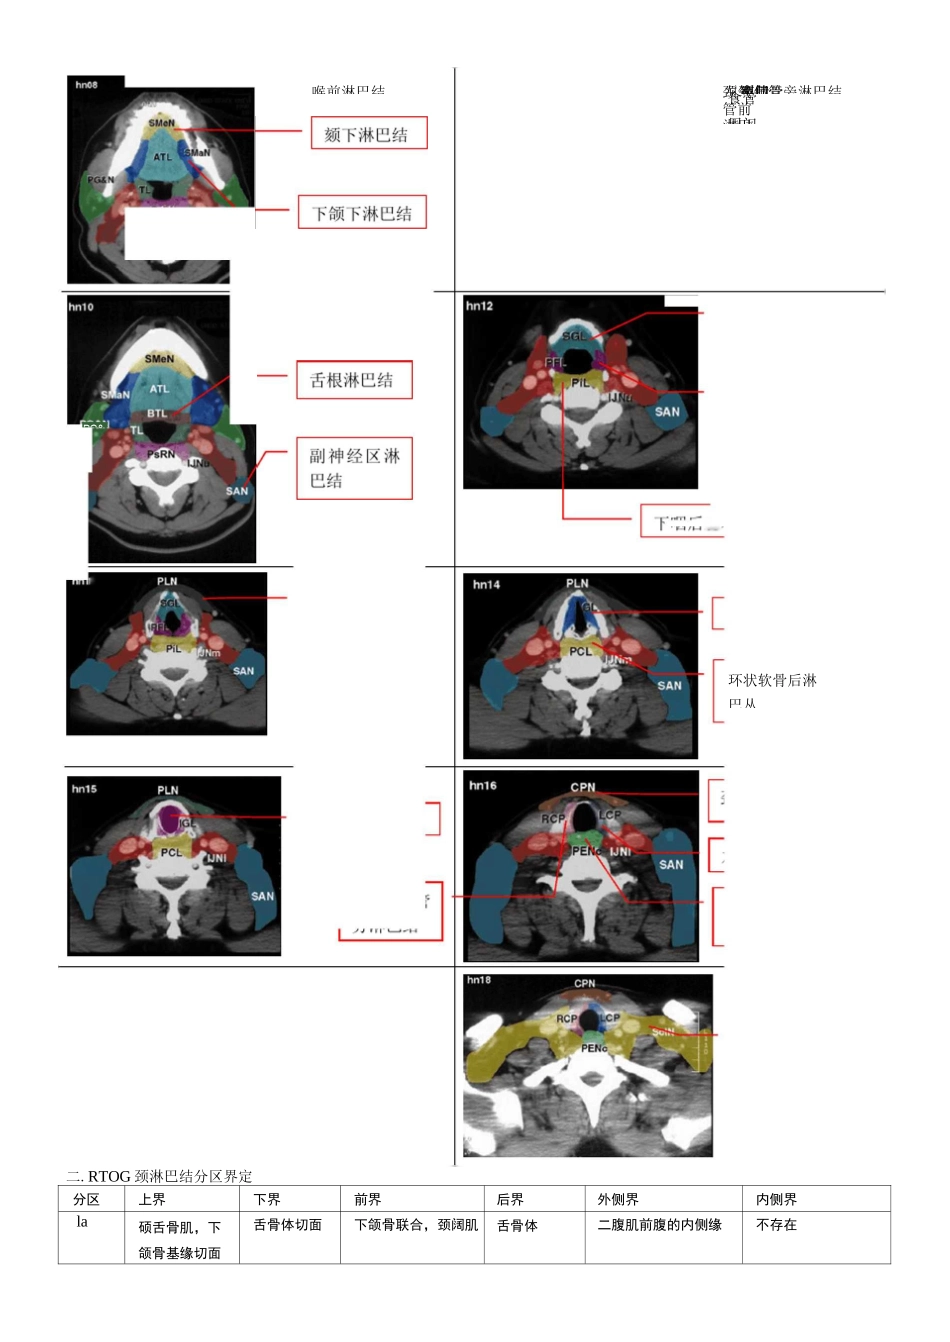

鼻旁耳前鼻咽淋巴结咽后淋巴结乳突全身淋巴结的分布与分组一.头颈部淋巴结:全身淋巴结约有 800 个左右,其中 200-300 个分布在头颈部,主要存在于颈部。临床上通过体检来判断颈部有无淋巴结肿犬转移是困难的,一般情况卞,成年人的颈部淋巴结均小又软,大多在 0.5cm 以下.颌下区由于口腔及咽部经常有外界感染,淋巴结较肿大,可在 2cm 左右。颈内静脉淋巴结,副神经淋巴结,锁骨上淋巴结这三组淋巴结彼此有淋巴管沟通,形成头颈部主要汇流区。颈淋巴结廓清手术也主要切除这三组淋巴结。双锁骨上淋巴结为全身淋巴系统的最后汇流处。这一位置的淋巴结转移对头颈部肿瘤来说为区域转移;对全身肿瘤来说,即为全身转移,预后恶劣。通常转移至右侧者,人多为横膈以上器官原发,转移至左锁骨上者,因胸导管汇流,大多为胸腔及腹腔、盆腔、下肢等原发。hn04前舌淋巴结软腭淋巴结扁桃硬腭淋巴丛腮腺颈内静脉卜•咽后壁和咽后淋巴结声门下淋巴系统左颈气管二.RTOG 颈淋巴结分区界定分区上界下界前界后界外侧界内侧界la硕舌骨肌,下颌骨基缘切面舌骨体切面下颌骨联合,颈阔肌舌骨体二腹肌前腹的内侧缘不存在声门梨状喉前淋巴结声门颈气管前淋巴左颈气管旁淋巴结锁骨PG&食管周闱环状软骨后淋巴丛体中线Ib下颌舌骨肌,下颌下腺上缘舌骨中心平面下颌骨联合,颈阔肌下颌下腺后缘下颌骨基底缘/内侧缘,颈阔肌二腹肌前腹外侧缘Ila颈 1 椎体横突下缘舌骨体下缘下颌下腺后缘,颈内动脉前缘,二腹肌后腹后缘颈内静脉后界胸锁乳突肌内侧缘颈内动脉内侧缘,脊柱旁肌(肩胛提肌)IIb颈 1 椎体横突下缘舌骨体下缘颈内静脉后缘胸锁乳突肌后界胸锁乳突肌内侧缘颈内动脉内侧缘,脊柱旁肌(肩胛提肌)III舌骨体下缘环状软骨下缘胸骨舌骨肌后外侧缘,胸锁乳突肌前缘胸锁乳突肌后缘胸锁乳突肌内侧缘颈内动脉内侧缘,脊柱旁肌(斜角肌〉IV环状软骨下缘胸锁关节上两公分胸锁乳突肌前内缘胸锁乳突肌后缘胸锁乳突肌内侧缘颈内动脉内侧缘,脊柱旁肌(斜角肌〉V舌骨体上缘CT 上出现颈部横向血管胸锁乳突肌后缘斜方肌前外侧界颈阔肌,皮肤脊柱旁肌(肩胛肌,头夹肌〉VI甲状软骨体下缘胸骨柄皮肤,颈阔肌气管食管间隙甲状腺内缘,皮肤和胸锁乳突肌前内侧缘不存在咽后淋巴结颅底舌骨体上缘咽部粘膜下筋膜椎前肌(颈长肌、头长肌)颈内动脉内侧缘体中线分区上界下界前界后界外侧界内侧界咽后淋巴结颅底舌骨体上缘咽部粘膜下筋膜椎前肌(颈长肌.头长肌)颈内动脉内侧缘体中线...